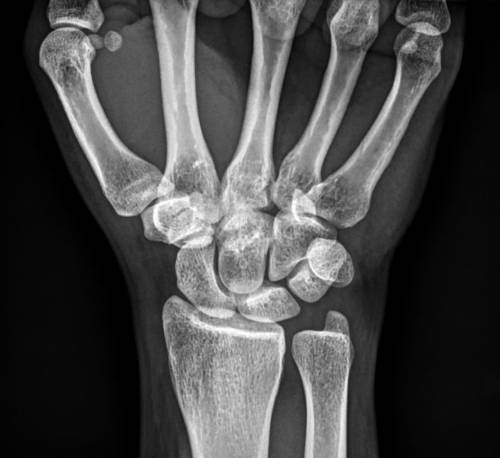

El esqueleto del caos cuántico

Un sistema cuántico queda perfectamente caracterizado cuando se conocen sus niveles de energía y sus autoestados. Investigadores de la UPM han participado en el desarrollo de un nuevo método para calcular autoestados cuánticos basado en el uso de órbitas periódicas que actúan como un esqueleto oculto de forma semejante a cómo lo hacen los huesos con nuestros cuerpos. (Más detalles en nota de prensa)